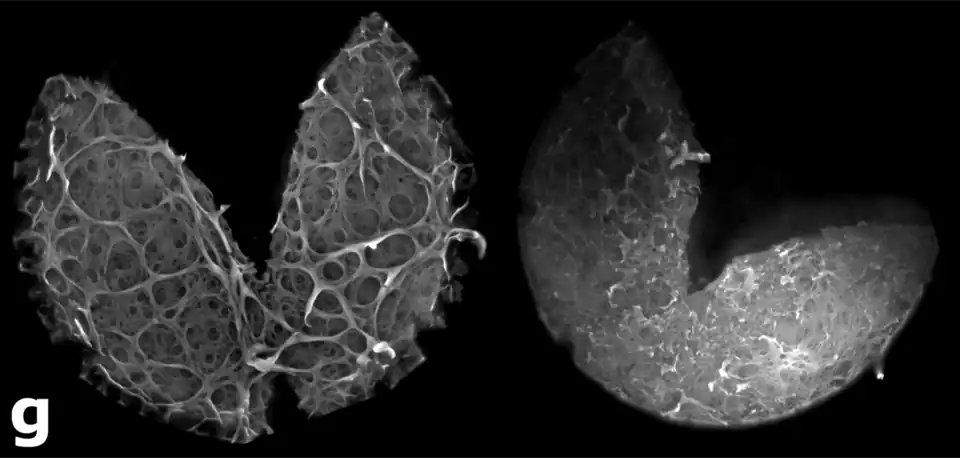

Zona pelúcida vacía, en etapa de eclosión del blastocisto. Microscopio confocal

Durante el quinto día del desarrollo del embrión, la zona pelúcida se irá degenerando por medio de una serie de ciclos de expansión y contracción; como también por la acción de enzimas, para dar paso a la implantación. El blastocisto, a través de varios procesos debe deshacerse de la Zona pelúcida (ZP) antes de la implantación. Las anormalidades intrínsecas de la ZP, son uno de los factores que limitan la reproducción en los seres humanos.

Este fenómeno recibe el nombre de eclosión. El embrión en estado de blastocisto, al eclosionar de la zona pelúcida, se llamará embrión o blastocisto implantado.